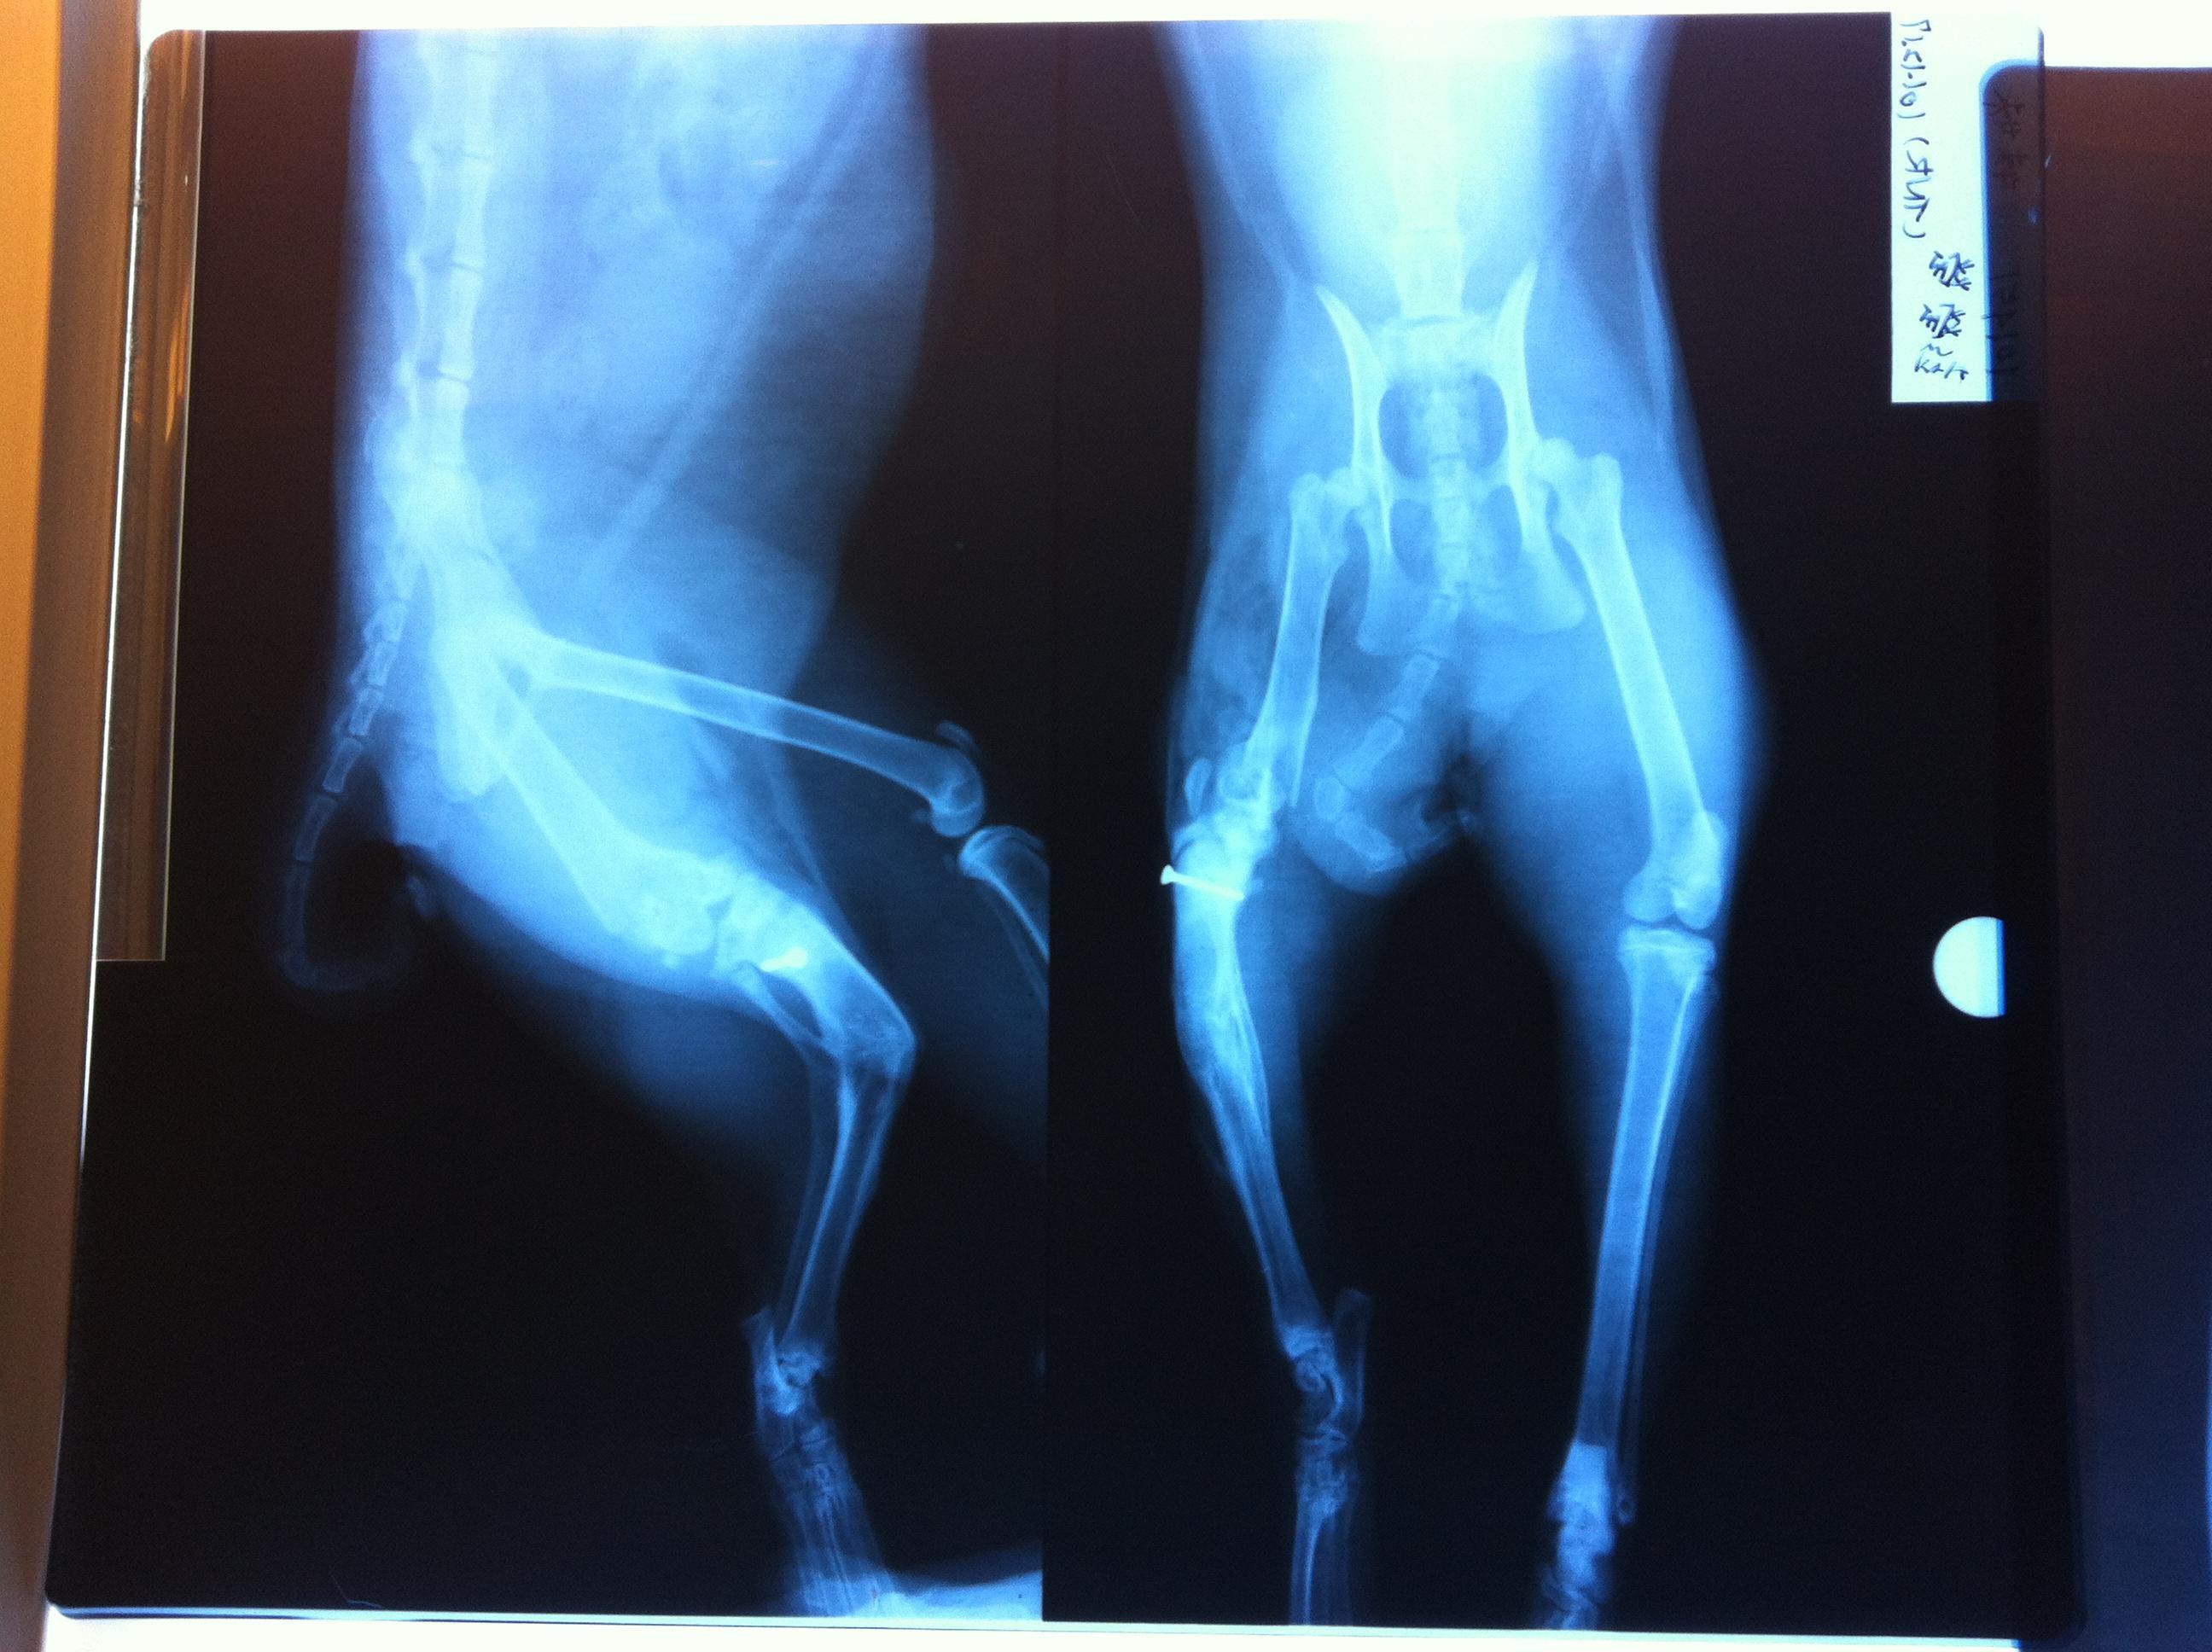

主題: 後腿二處斷裂的小橘妹妹 申請者姓名: 彭瑩瑩 花色: 申請日期: 2012-12-25 00:33:53 申請者部落格: 申請者臉書網址: 所在縣市/合作醫院: 桃園縣/思邁爾動物醫院 治療費用: 28000元 需求人數: 30人 已結案 (2013-08-06 13:45:45) 報名人員: Jerry(已付款)、May Chuang(已付款)、丁小丁(已付款)、Cherry Hsu(已付款)、Eli Tsao(已付款)、Eli Tsao(已付款)、游妃妃(已付款)、Ma Yi(已付款)、杜杜(已付款)、leezu(已付款)、Lin YC(已付款)、Eliza Chen(已付款)、Wanhua Chan(已付款)、Molly Cheng(已付款)、Doris Chen、Yu-Chen Lee(已付款)、miraai(已付款)、陳阿條(已付款)、Mia Wei(已付款)、存錢筒(已付款)、丁小乖(已付款)、周振禮(已付款)、Doris(已付款)、yin(已付款)、Andrea Lin(已付款)、Vickie(已付款)、Raymond Kuo(已付款)、田馨(已付款)、阿修(已付款)、Vozaponmi Cheer(已付款)、okina、Weirong(已付款)、 候補人員: 動物病情說明: 這隻橘妹妹是我在餵養的浪浪,受到不明外力的撞擊(疑似車禍)而造成後左腿的嚴重骨折:小腿和大腿都斷裂。

因為她非常膽小怕人,都是等我離開才敢出來吃大家剩下的,所以發現得很晚。等到發現時,她小腿的骨折已經自行接合,但卻是長成歪的,大腿骨則裂成尖刺,刺進她的肉裡,關節也因而裂開脫離,也就是說她每走一歩路就有尖在刺,可憐的孩子就這樣拖著傷腿痛了不知道多少個日子!

手術是為了把關節移回原處,削除尖銳的裂骨,並打鋼釘固定。現在小橘妹妹很努力地修養,等候復元,希望大家可以幫忙她的手術費用。